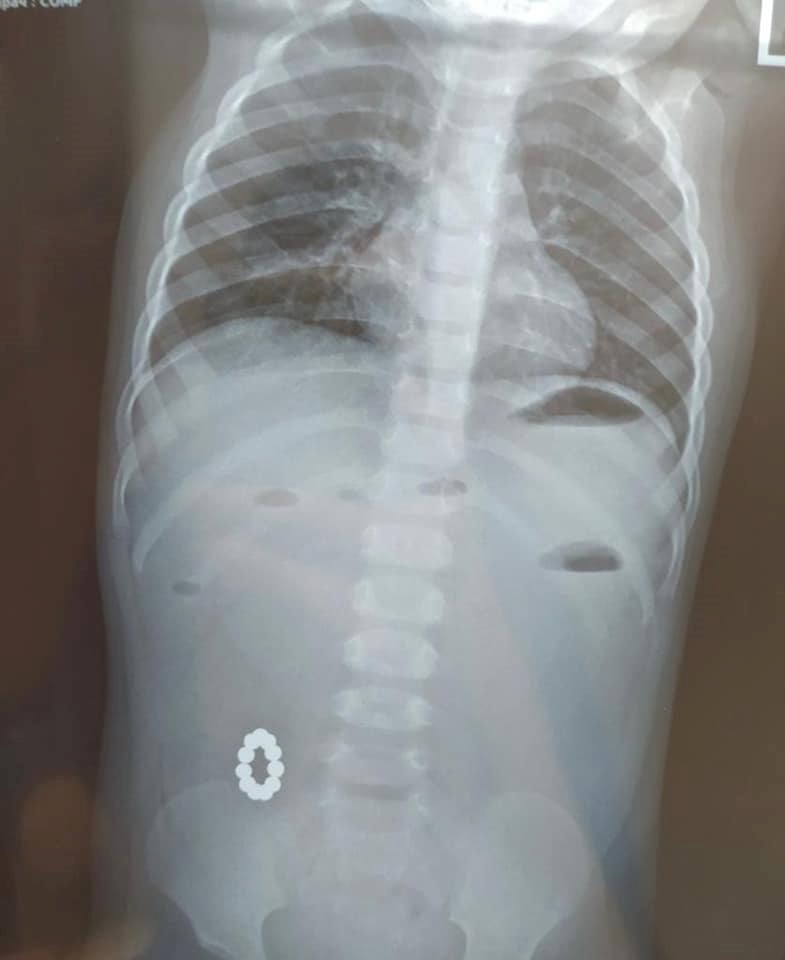

В Харькове годовалая девочка проглотила 11 магнитов, которые соединились между собой в кишечнике и образовали кольцо. Ребенку пришлось делать операцию, сообщила накануне Харьковская областная детская больница №1.

"В нашу больницу была доставлена девочка 1 года с подозрением на пищевое отравление, но при доскональной диагностике были выявлены инородные тела кишечника. А именно – магниты, которые между собой соединились и образовали кольцо", – говорится в сообщении.

Объединенные магниты привели к тяжелой хирургической патологии – непроходимости кишечника. После сложной операции хирургам удалось удалить инородные тела и ликвидировать непроходимость кишечного пути.